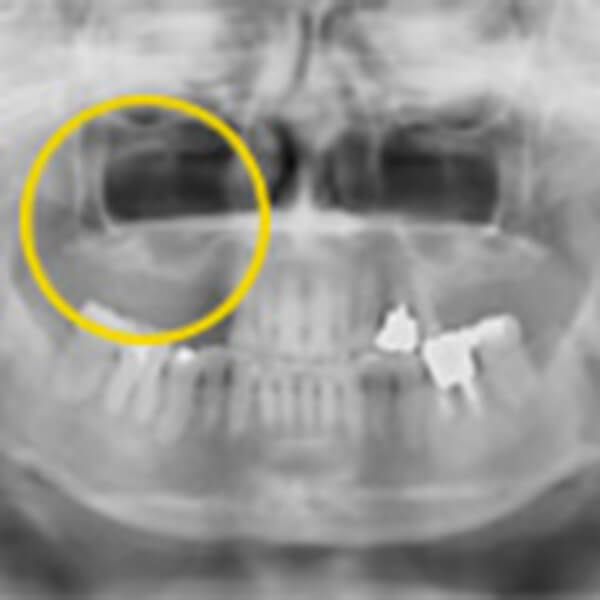

術前レントゲン画像

術前にレントゲンを撮影致します。

上の奥歯4本欠損

上の奥歯4本が欠損していることが分かりました。